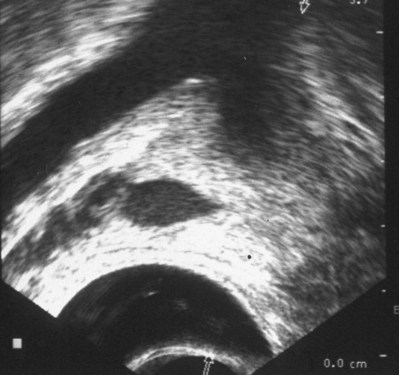

TRUS provides excellent definition of the prostate, seminal vesicles, ampulla of the vas deferens, and the ejaculatory ducts. TRUS is primarily employed to examine patients suspected to have ejaculatory duct obstruction (EDO). These patients usually have low-volume azoospermia (volume <1 mL) with acidic pH and negative semen fructose. TRUS typically employs the 5- to 7-MHz endocavitary probe with scanning in both the longitudinal and transverse planes. Careful examination of verumontanum may identify midline prostatic cysts such as müllerian or wolffian duct cysts or stones obstructing the ejaculatory duct (Fig. 21–2). Often the ejaculatory duct may not be well visualized, but dilation of the seminal vesicles serves as a de facto sign of ejaculatory duct obstruction. Although not always present with ejaculatory duct obstruction, seminal vesicle width in excess of at least 12 to 15 mm or ejaculatory duct diameter greater than 2.3 mm is considered suggestive of obstruction (Carter et al, 1989; Vazquez-Levin et al, 1994; Smith et al, 2008).

Figure 21–2 Transrectal ultrasound (sagittal image) demonstrating a dilated ejaculatory duct culminating in an ejaculatory duct cyst.